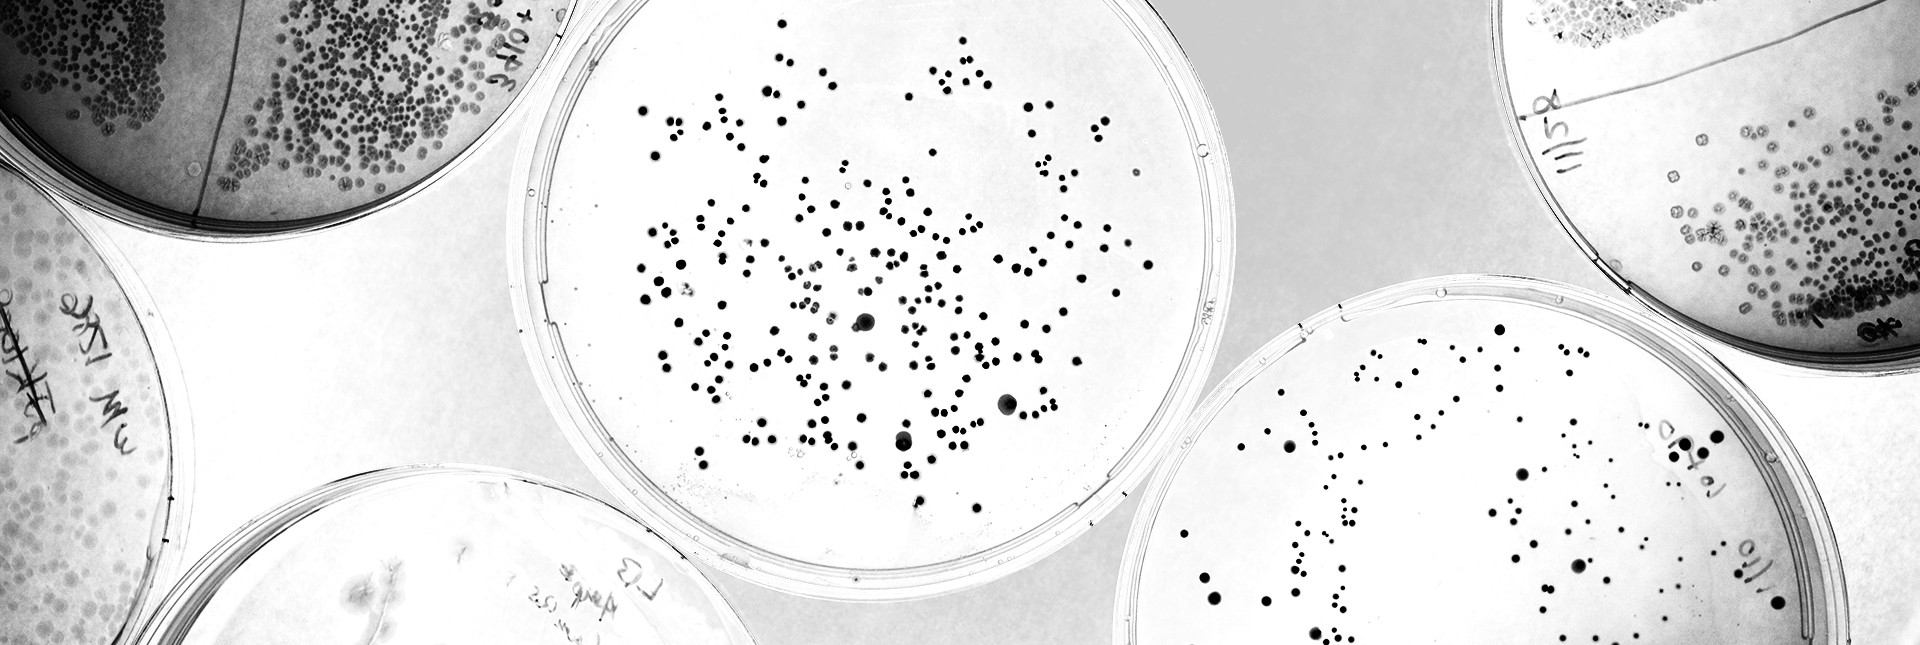

Research in Brian Cunningham’sprofessor of electrical and computer engineering (CGD leader) group also takes advantage of human-computer partnerships to evaluate data, using AI to help improve the detection of biomarkers—molecules that can indicate what is happening in the body, as well as the presence of disease. Their microscopy-based diagnostic technique generates red images with tiny black spots scattered throughout, each representing a single biomarker molecule tagged with a gold nanoparticle for visualization. Integration of a deep-learning algorithm helps to automate the counting of these spots, improving the accuracy and lowering detection limits of their method.

While the automation helps remove the need for expert analysis, the AI’s performance is tied with the quality of its training data. A speck of dust can be difficult to differentiate from a true biomarker spot, even to the trained eye. To ensure accurate counting, graduate student Han Lee spent hours cross referencing black spots against ground truth electron microscope images.